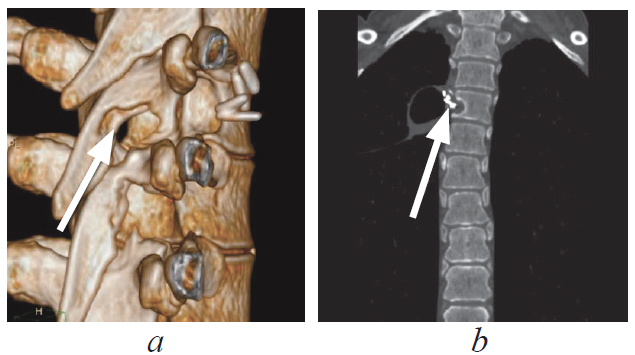

Paravertebral tumors of mediastinal localization — an extensive group of pathological processes, the surgical treatment of which is carried out by doctors of various specialties, such as neurosurgeons and surgical oncologists. Currently, thoracoscopic removal is considered to be the most preferred method of surgical treatment of these mass formations, in view of the least trauma, fewer complications, and a reduction in the time of postoperative recovery of patients. A clinical case of surgical treatment of a patient with a giant paravertebral tumor originating from the 4th thoracic root is presented. The tumor was an incidental finding during routine fluorography. There were no focal neurological symptoms. Taking into account the topographic and anatomical features of the volumetric formation, the patient underwent a combined two-stage surgical intervention, where the first stage was laminectomy and removal of the foraminal component of the tumor from the posterior approach, the second stage was single-port video-assisted thoracoscopic removal of the mediastinally located tumor fragment. The operation was performed under conditions of a collapsed lung on the side of the intervention. In the postoperative period, no neurological deficit was noted; according to the control introscopy, the tumor was removed completely. According to the results of histological examination – neurofibroma (Grade I).